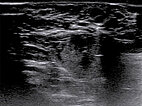

Es wird zur endgültigen Diagnosesicherung jetzt noch eine sonogesteuerte Stanzbiopsie mit einer 16-Gauge-Einmalbiopsiepistole aus der Läsion am Labium majus rechts entnommen. Die in die Läsion vorgeschobene Biopsienadel erzeugt eine starke distale Schallauslöschung im B-Bild-Ultraschall.